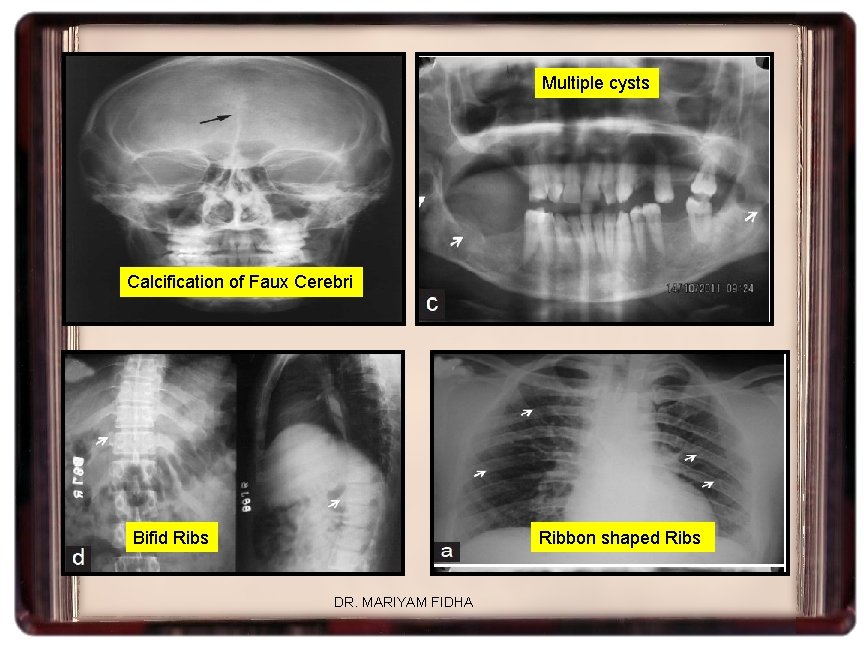

• Multiple OKCs are asso. with NEVOID BASAL CELL CARCINOMA SYNDROME • • Gorlin Goltz Syndrome Jaw cyst-Basal Cell Nevus syndrome Bifid rib Syndrome Hereditary cutaneomandibular polyposis • First described by Binkly & Johnson, 1951 • Autosomal dominant trait • Caused by mutation in Patched gene(PTCH) a tumor suppressor gene • 9 q 22. 3 – q 31 DR. MARIYAM FIDHA

CLINICAL FEATURES I)JAW AND SKULL • OKC calcified faux cerebri • Large calvaria • Large paranasal sinuses • Hypertelorism • Bridging of the sella turcica • Cleft lip and palate III) AXIAL SKELETAL ABNORMALITIES • Rib abnormalities • Spina bifida • Short 4 th metacarpel • Lumbarization of sacrum • Pseudocysts of phalanges II) SKIN & INTERNAL ORGANS • Basal cell carcinoma • Epidermoid cysts • Palmar- plantar pits • Calcified ovarian fibromas • Subcutaneous calcifications IV) CNS • Medulloblastomas • Congenital hydrocephalus • Mental deficiency • Craniopharyngioma • meningioma DR. MARIYAM FIDHA

Multiple cysts Calcification of Faux Cerebri Bifid Ribs Ribbon shaped Ribs DR. MARIYAM FIDHA